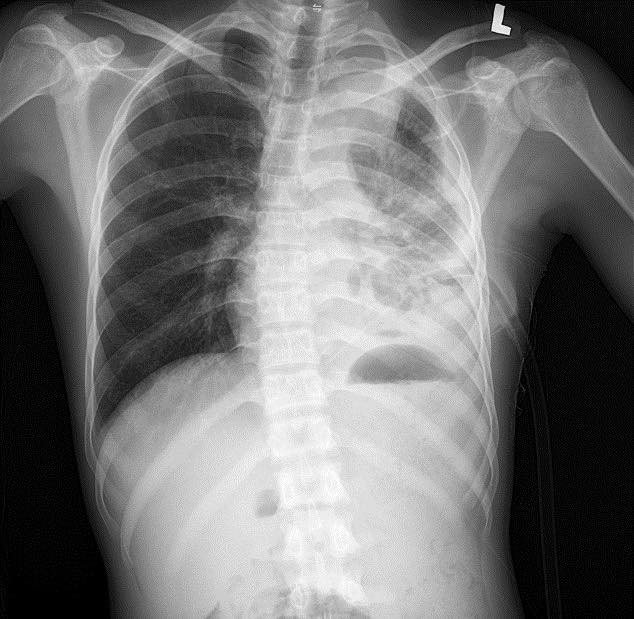

mang-phoi-2.jpg

Tổn thương phổi trên phim chụp - Ảnh BVCC

Kết quả xét nghiệm máu cho thấy tình trạng nhiễm trùng nặng với chỉ số bạch cầu (WBC) lên tới 64.8 G/L, chỉ số CRP cao 263.6 mg/dL. Với hệ thống chẩn đoán hình ảnh hiện đại, các bác sĩ ghi nhận: Đông đặc nhu mô thùy dưới phổi trái, tràn dịch màng phổi trái lượng nhiều, tràn khí màng phổi trái, phổi trái bị xẹp thụ động, đẩy lệch trung thất sang phải.